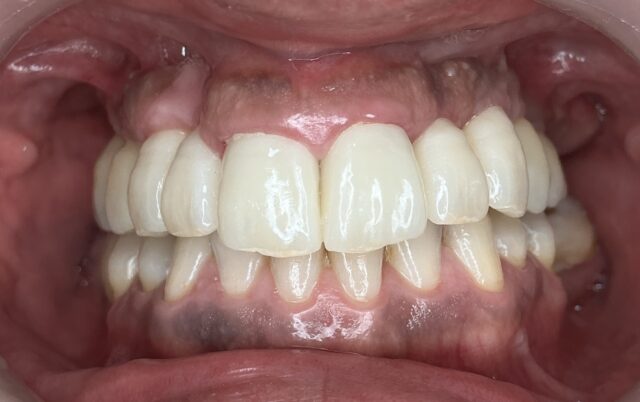

AFTER

術後